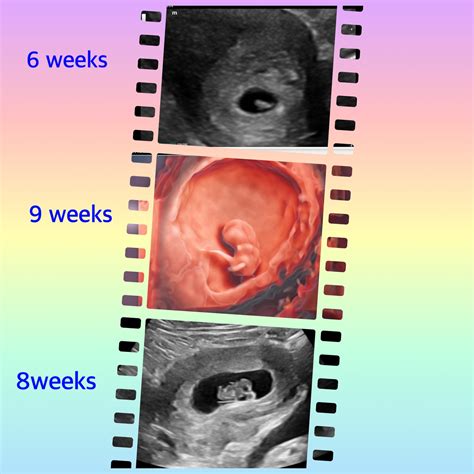

At 8 weeks, the fetus is still very small, but several key structures can be visualized:

• Gestational Sac: A fluid-filled structure that contains the developing embryo.

• Yolk Sac: A small, round structure that produces blood cells and helps in the early development of the embryo.

• Embryo: The developing fetus, which is about the size of a raspberry at this stage.

• Heartbeat: The fetal heartbeat is usually detectable and can be seen as a rapid flickering on the ultrasound screen.

• Neural Tube: The early stages of the brain and spinal cord can be observed.